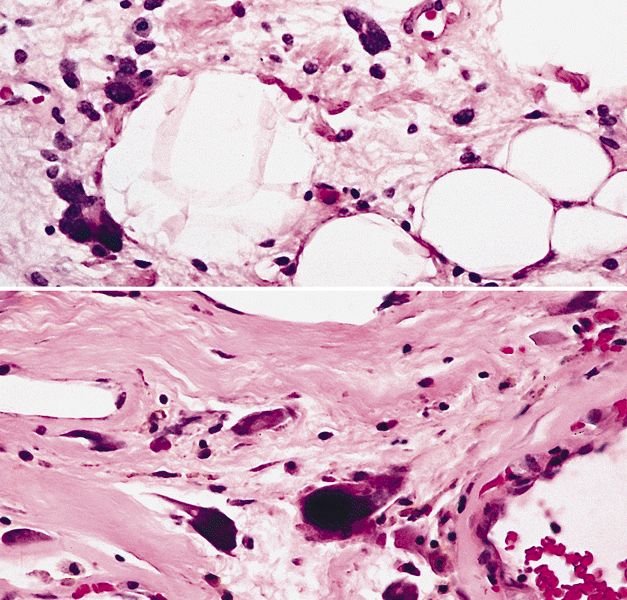

Contributed by Michael Clay, M.D., Melanie Bourgeau, M.D. and AFIP

Morphologic variability:

Metaplastic change:

Microscopic (histologic) description

- Depends on subtype, generally composed of mature fat with variably sized adipocytes and bands of fibrotic stroma containing spindle cells with enlarged, hyperchromatic nuclei

- Can be markedly atypical

- Cellularity is low and mitotic figures are uncommon

- Atypical cells are more commonly found in fibrous septa and in a perivascular distribution

- Sclerosing subtype

- Second most common subtype

- Predilection for retroperitoneal or paratesticular location

- Collagenous fibrous tissue with scattered adipocytes and atypical multinucleated stromal cells

- Scant lipogenic component may be missed in small samples

- Inflammatory subtype

- Rare

- Almost always in the retroperitoneum where it is confused with nonlipogenic tumors

- Chronic inflammatory cells (B > T cells) with occasional lymphoid follicles scattered in a cellular fibrocollagenous stroma with sparse multinucleated atypical cells

- May obscure adipocytes